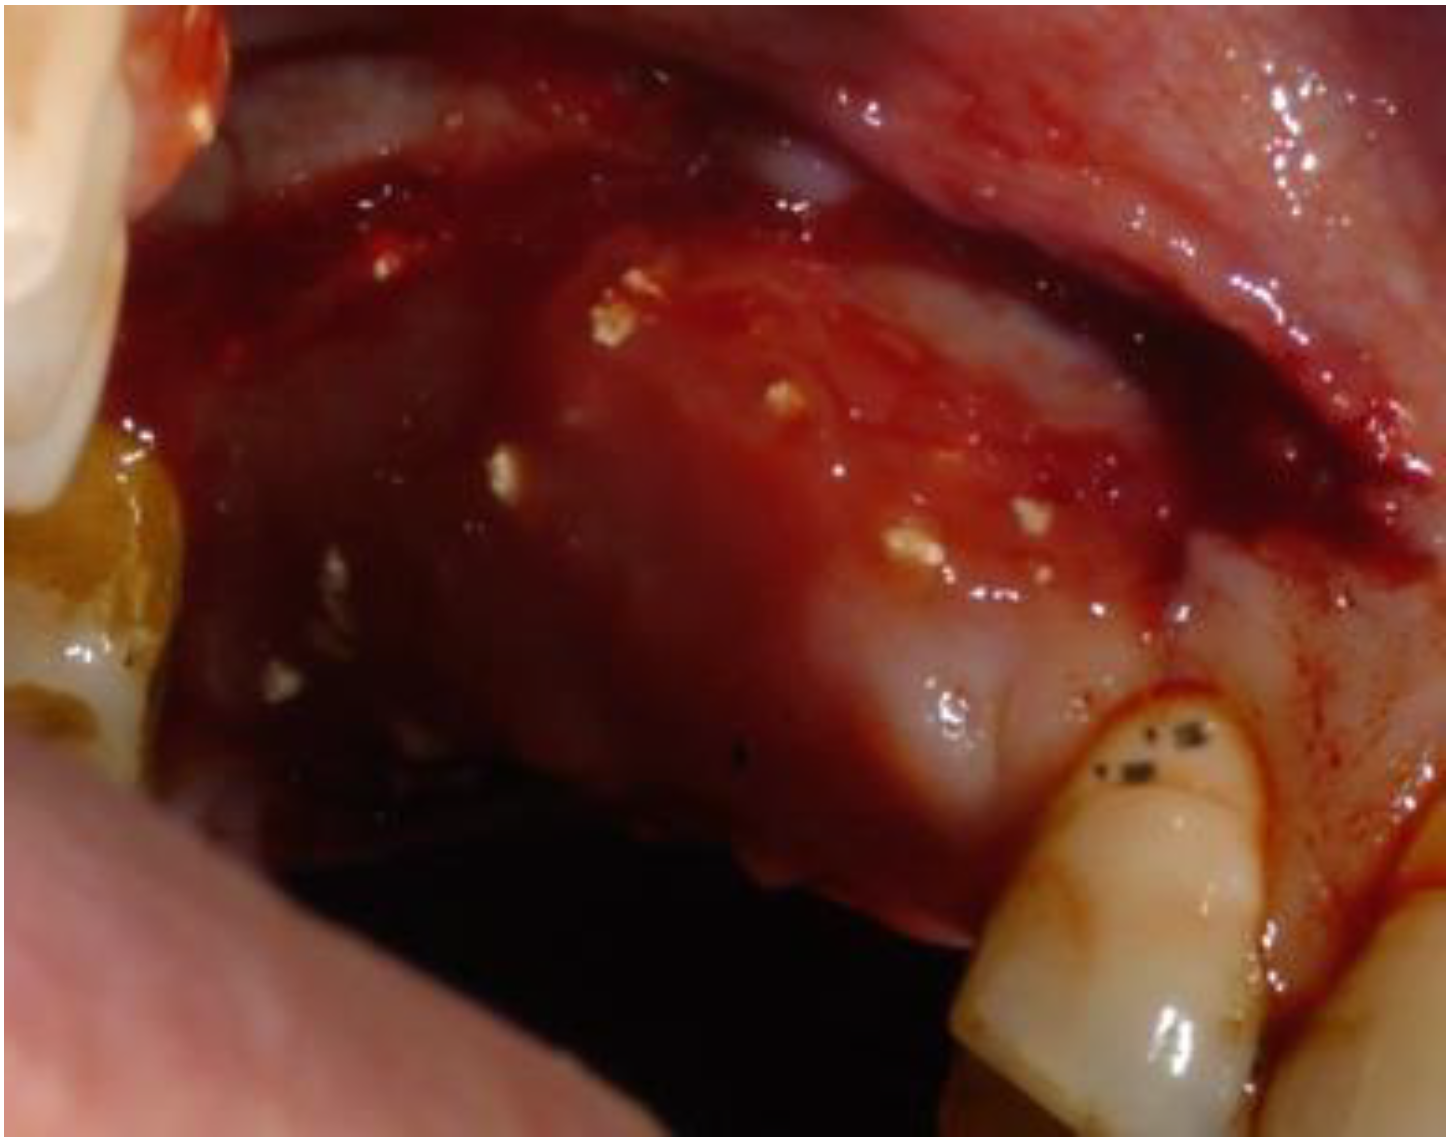

2.1. Clinical and Surgical Procedures